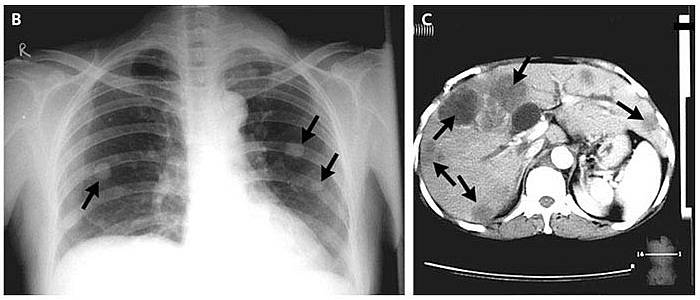

Plain radiography of the chest showed multiple nodular opacities in both lungs (Panel B, arrows). Computed tomography of the abdomen revealed multiple lesions in the liver (Panel C, arrows).